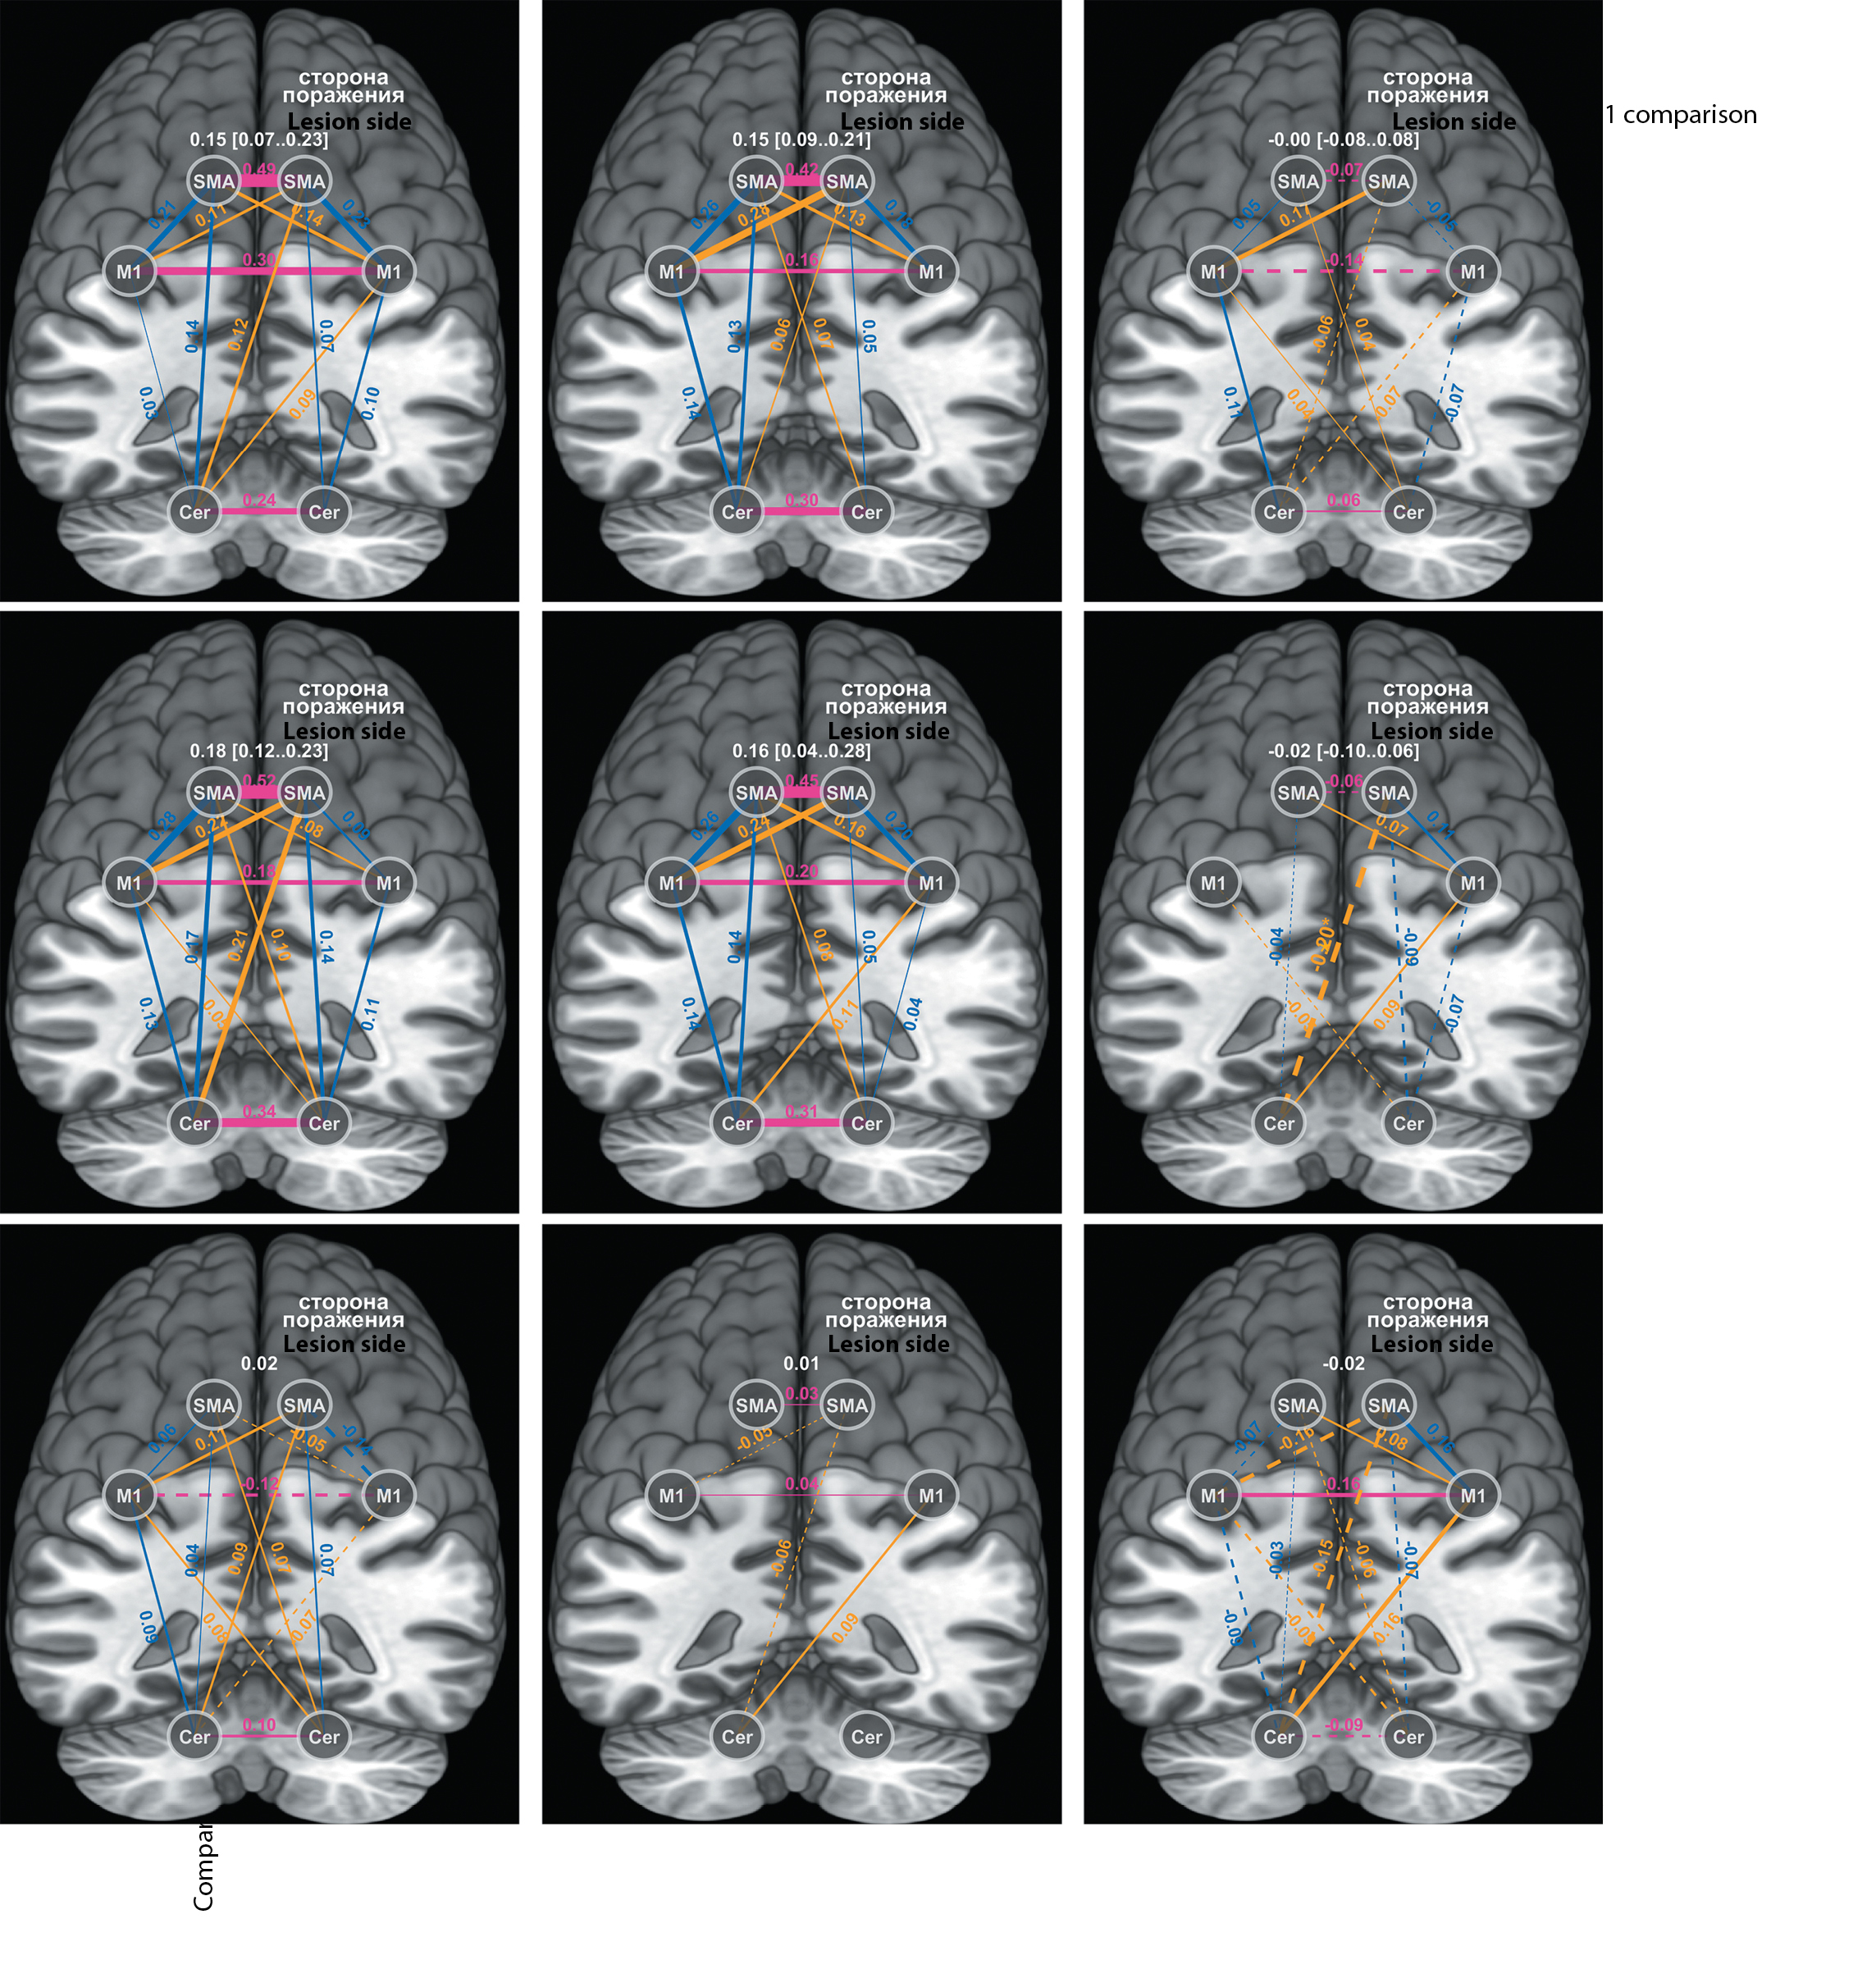

До лечения (тест 1) моторная сеть в состоянии покоя (фМРТ покоя) характеризовалась средней внутрисетевой связностью 0,18 в основной группе и 0,15 — в контрольной (p > 0,05). Исходных межгрупповых различий во взаимосвязях конкретных узлов внутри сети не было. К концу лечения (тест 2) достоверно ослабела связность SMA повреждённого полушария с противоположным Cer в основной группе; в остальном наблюдались лишь тренды (рисунок). В контрольной группе мы отметили тенденцию к ослаблению связности ипсилатеральной М1 с М1 противоположной стороны и с SMA — своей стороны (рисунок, верхний ряд). У пациентов основной группы взаимосвязь М1–М1 не изменилась; связность ипсилатеральной М1 стала сильнее с SMA обоих полушарий и с противоположным Cer (рисунок, средний ряд).

Матрицы ФС моторной сети у пациентов основной и контрольной групп до и после лечения. Регионы интереса обозначены белыми кругами; цветами выделены их взаимосвязи: розовым — межполушарные поперечные, оранжевым — межполушарные диагональные, синим — внутриполушарные; толщина линий между регионами схематично отражает силу функциональных связей (пунктиром показано ослабление связи); цифры над линиями обозначают коэффициент корреляции ρ. В правой и нижней частях рисунка приведены результаты сравнения ФС до и после курса лечения (внутри- и межгруппового соответственно). Цифры белого цвета над каждой матрицей отражают среднее значение внутрисетевой связности (или разницу её внутри и между группами — в правой и нижней частях рисунка соответственно), в квадратных скобках указан доверительный интервал для этого среднего с уровнем доверия 0,95. *p < 0,05 (тест Стьюдента)

FC matrices of motor networks in the main and the control groups prior to and after the treatment. The white circles designate the regions of interest, the colored lines indicate their connections. The rose lines represent interhemispheric

cross-lateral connections, the orange lines represent interhemispheric diagonal connections, and the blue lines represent intrahemispheric connections. The strength of the functional connections is proportional to the width of the lines, with weaker connections indicated by dotted lines. The correlation coefficient (ρ) is shown above the lines. The results of FC comparison before and after the treatment are presented on the right and on the lower panels, within and between the groups, respectively. Digits in white above each matrix reflect the mean value of the intranetwork connectivity or the difference in its level within or between the groups: on the right and on the lower panels, respectively. The confidence interval of 0.95 for this mean value is shown in the brackets. *p < 0.05 (using Student's t-test).

Клинико-сетевые корреляции

Корреляционный анализ показал прямую зависимость в тесте 2 для всех больных между силой межполушарной связности М1 и результатами FM-UE (ρ = 0,87; p < 0,005), ВВТ (ρ = 0,72; p < 0,01) и динамометрии (ρ = 0,69; p < 0,01). В тесте 1 сила взаимосвязи М1–М1 слабо коррелировала с ВВТ (ρ = 0,45; p < 0,05). Для связи SMA справа и Cer слева к завершению курса обнаружена обратная зависимость с результатами ВВТ и FM-UE (для обоих ρ = –0,44; p < 0,05).

В нашем исследовании межполушарная связность М1 в контрольной группе к концу курса физической реабилитации ослабла, в то время как в основной она не менялась или характеризовалась тенденцией к усилению. Одновременно в группе ИСМ укрепилась внутриполушарная связь М1–SMA на стороне инсульта; в контрольной группе такой тенденции не отмечено (рисунок). При этом результаты функциональных тестов (ВВТ, FM-UE и динамометрия) прямо коррелировали с силой межполушарной связи М1–М1.

Мозжечок участвует в моторном обучении и далее — в моторном контроле уже сформированного навыка [36]. Мы наблюдали укрепление взаимосвязи М1 повреждённого полушария с противоположным Cer у больных основной группы и ослабление ФС ипсилатеральной SMA с обоими полушариями Cer у всех больных (рисунок). В какой мере такие тенденции обусловливают успешность моторного обучения после инсульта, не вполне понятно, хотя мы выявили обратную корреляцию результатов функциональных тестов с силой связи SMA повреждённого полушария с противоположным Cer.